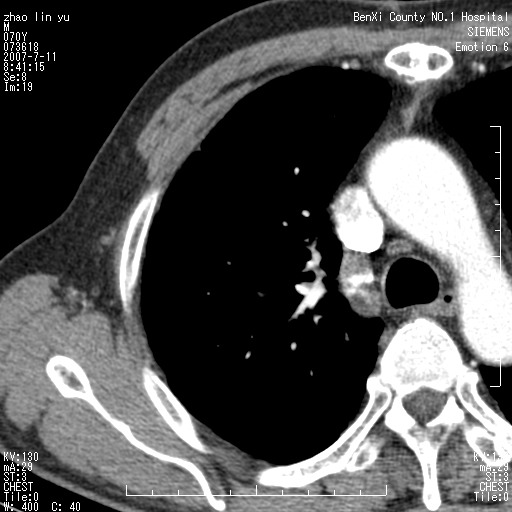

以下是引用王靖旗在2007-7-10 17:12:00的发言:[br] 男、70、咳嗽两个月,半年前换瓣手术,胸片未见异常,于昨天行x片发现右肺上野大片影,行ct扫描,这里是减薄图像,余肺正常。明天晚上会有增强扫描片,到时我会上传。[br][br] 冠状位请大家细看,应该是有意义的,[br][br] 请大家先看平扫发表意见。[br][br]

以下是引用zhangzhongshou在2007-7-10 21:43:00的发言:[br]右肺上叶周围型肺癌,以孤立型细支气管肺泡癌可能性大。